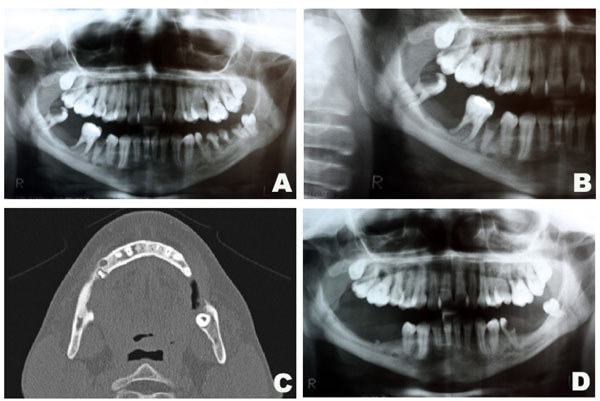

Intraoral assessment showed high levels of plaque and calculus, severe periodontitis with edematous gingiva, absence of tooth # 47, dental caries and a hyperplasic purplish lesion in the lingual aspect localized adjacent to the teeth 32, 33 and 34 (Fig. 1A). There was also a purplish tumoral lesion in the posterior alveolar ridge between teeth # 46 and 48 (Fig. 1B). The panoramic x-ray image of this area (Fig. 2A and 2B) revealed a nonspecific ill-defined rarefaction, without evidence of sclerosis at the margins. Widening of the periodontal ligament space, lamina dura destruction, and narrowed roots were present in those teeth. The axial computed tomography (CT) image (Fig. 2C) demonstrated that such lesion was non-expansible and extended to the mandibular canal. In addition, the lingual cortical and the alveolar bone were destroyed as confirmed by the coronal CT.

Clinical aspects of the peripheral (A) and central giant cell lesion (B).

Radiographic aspects of the central giant cell lesion. Panoramic x-ray depicting the lesion in the mandible (A and B). Axial CT showing bone destruction of the rigth side of the mandible measuring 13x5mm (C). Panoramic x-ray after 1 year of follow-up (D).